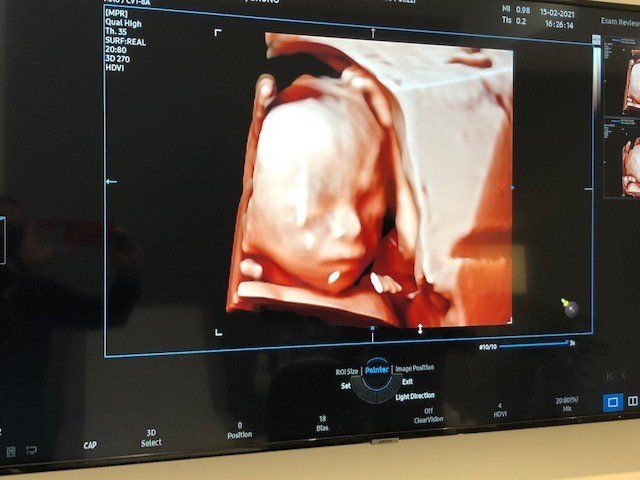

e’ specializzato in Ostetricia e Ginecologia. In campo Osterico esegue Ecografie del Primo trimestre, screening, esame premorfologico della gravidanza a rischio, ecografia morfologica di primo e secondo livello con studio cardiaco fetale, ecoflussimetria, valutazione ecografica in 3d e 4d con registrazione su supporto digitale DVD o Pen Drive per le pazienti. In campo ginecologico ecografia di primo, secondo livello e studio delle Masse Ovariche secondo le linee guida internazionali IOTA.

Lo specialista in Ostetricia per le pazienti in dolce attesa propone un piano di controllo estremamente dettagliato, ad esempio oltre alla classica ecografia che solitamente viene eseguita nei primi mesi della gravidanza, si esegue anche l'esame premorfologico per le gravidanze a rischio, in modo da valutare fin dai primi mesi la probabilità di malformazioni ed ecografia 3d e 4D con registrazione su supporto digitale delle immagini e del suono del battito cardiaco. Si effettua lo studio cardiaco fetale, tutto ciò consente di monitorare e tutelare la salute della madre e del bimbo.